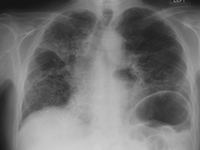

RT de fibrosis masiva progresiva debido a exposición a la sílice o al carbón

De la colección personal de Kenneth D. Rosenman, Michigan State University